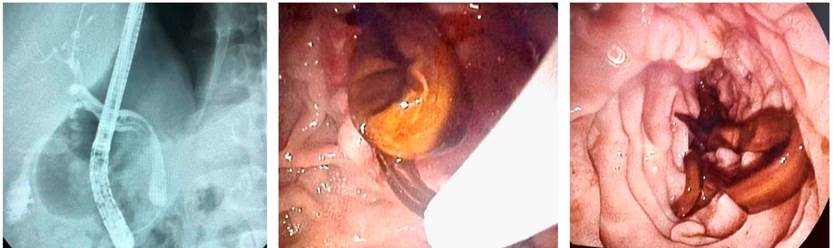

Como estudio complementario, se realizó una ecografía abdominal, en la cual se evidenció la presencia de pólipo vesicular y barro biliar, sin alteraciones a nivel de la vía biliar. Debido al riesgo intermedio de coledocolitiasis, por el aumento de las bilirrubinas totales, la alteración del perfil hepático, la clínica de pancreatitis biliar (Tabla 1) y mayor sensibilidad para microlitiasis, se practicó una ultrasonografía endoscópica que reportó colelitiasis asociada a imagen y fue compatible con AL a nivel de la luz del colédoco, con estructura alargada tubular hiperecogénica, que no daba sombra acústica, e imagen en doble riel (Figura 2). Se indicó un manejo con albendazol (400 mg vía oral, cada 24 h por 3 días) y se efectuó una CPRE, sumada a una papilotomía y a la extracción de áscaris a nivel de la vía biliar, sin complicaciones posoperatorias (Figura 3).